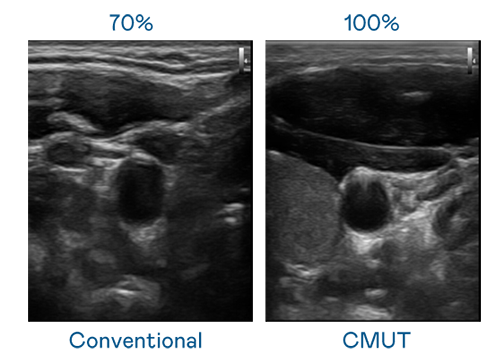

CMUT 技术是一种用电容式微机电元件来产生超音波讯号的技术。与传统 PZT 压电式技术相比,CMUT 频宽增加 30%,更宽频的超音波讯号让影像解析度大幅提升,是实现高影像品质医疗超音波扫描、促进精准医疗发展的关键技术。

大频宽带来超清晰影像

超音波影像的解析度高低,首先取决于探头能发出的讯号频宽。凯发天生一触即发 CMUT 可提供高清晰的超音波讯号,提供高频宽、高灵敏度、影像纹理细节更高的超音波影像,协助医护人员缩短影像判读时间及利用精准的医疗影像进行诊断。